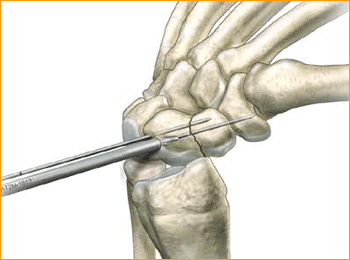

Dorsal Scaphoid Technique for 2.5 mm, 3 mm, 3.5 mm and 4 mm Headless Compression screws.

1. APPROACH AND NEEDLE INSERTION

The entry point in the proximal pole is at the tip of the scaphoid immediately adjacent to the scapholunate ligament. This can be located either using an arthroscopy or mini open dorsal approach between the third and fourth extensor compartments. Whichever approach is employed, it is essential to ensure that the guide wire does not transfix an extensor tendon.

Having established the entry point, introduce the appropriate guide wire aiming for the base of the thumb and check the position on the fluoroscope. Aim to place the leading edge of the guide wire in the subchondral surface of the distal pole of the scaphoid. Confirm the wire placement and depth under imaging.

2. FRACTURE STABILIZATION

If the fracture is unstable it may be helpful to place a second parallel guide wire using the parallel wire guides.

3. DETERMINE SCREW LENGTH

Measure guide wire length using either the percutaneous screw sizer, or by placing a second wire at the entry point and subtracting the difference. The screw sizer cannot be used with the arthroscopic technique due to the limited access. Subtract 4 mm from the measured length to ensure that both ends of the screw are buried within the bone.

4. ADVANCE GUIDE WIRE

Advance the guide wire through the far cortex so that it lies in the subcutaneous tissues. This minimizes the risk of accidental withdrawal of the guide wire while drilling and facilitates wire removal if it should break.

Tip: For most adult males the screw should not be longer than 26 mm, and in females 22 mm.

5. DRILL NEAR CORTEX

Open the near cortex with the appropriate profile drill.

6. DRILL FAR FRAGMENT

Next, drill into the far fragment with the long drill. To be effective the drill only has to advance 4–5 mm past the fracture site.

Tip: The long drill is recommended to mitigate the effects of varying bone density and distraction upon screw insertion.

7. SCREW INSERTION

Insert the correctly sized screw with the appropriate hex driver. If resistance is met upon insertion or if distraction occurs, stop, remove the screw, redrill with the long drill, and re-insert the screw. Confirm placement and length of the screw on imaging, ensuring that both leading and trailing edges of the screw are beneath the articular surfaces. Finally remove the guide wires.